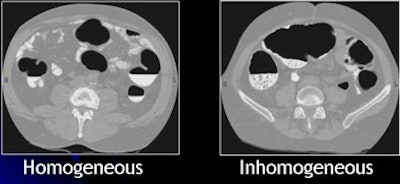

| Inhomogeneous tagging often appears in reduced or nonlaxative CTC. The uneven appearance of tagged materials on CTC data represents a mixture of semisolid fecal materials, air bubbles, fat, undigested foodstuffs, and unevenly distributed contrast agents. |

Inhomogeneous tagging often appears in reduced or nonlaxative CTC data, resulting from a mixture of semisolid fecal materials, air bubbles, fat, undigested foodstuffs, and unevenly distributed contrast agents.